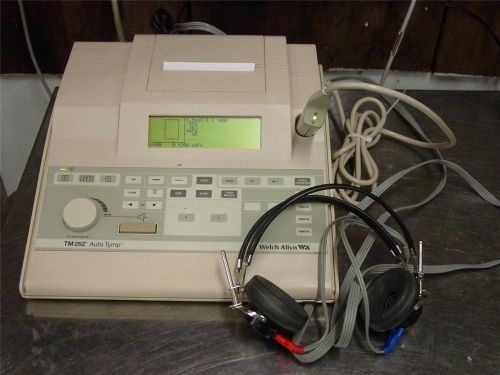

Welch Allyn TM262 AutoTymp Tympanometer Audiometer v-4 GSI 38 - TM 262